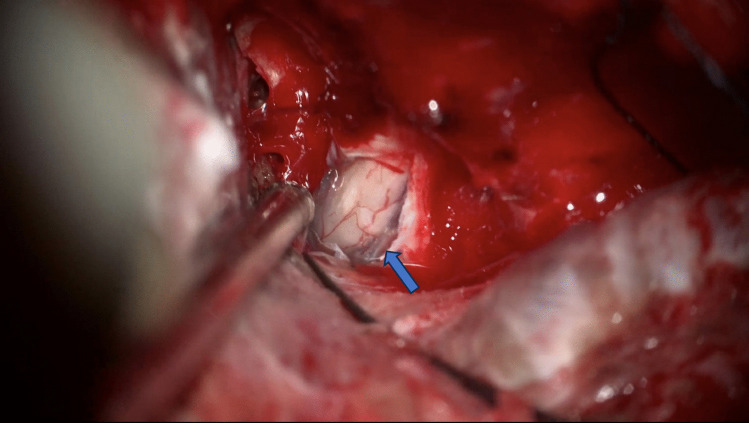

Abstract Image

Purpose: Optic canal decompression is a surgical option in anterior skull base tumors with optic nerve involvement. Meningiomas may grow into the optic canal even without evidence of involvement on MRI studies. We aim to investigate the effect of routine optic canal unroofing performed by skull base trained surgeons versus general neurosurgeons on the postoperative visual outcomes in anterior skull base meningiomas.

Conclusion: Patients with tuberculum sellae and anterior clinoid process meningiomas benefit from skull base surgeons trained in extradural optic canal decompression, as reflected by lower postoperative secondary visual acuity deterioration in patients treated by skull base trained surgeons. All cases presenting with tumors with optic apparatus involvement should be managed by skull base trained surgeons to maximize postoperative visual acuity preservation.